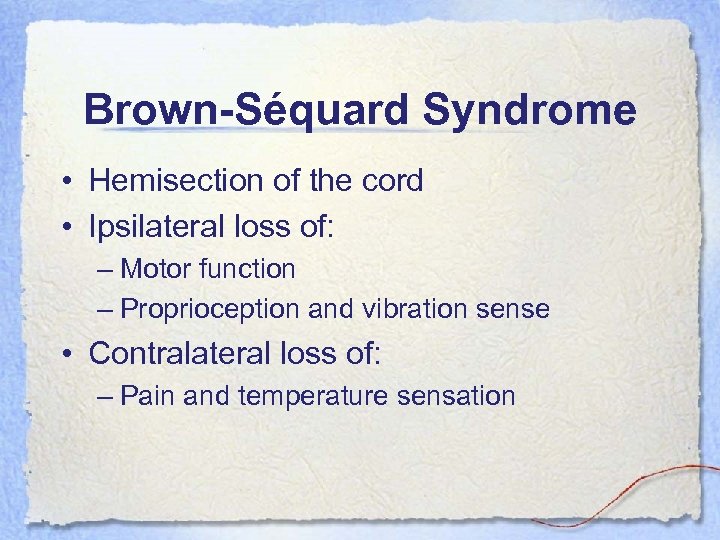

Brown-Séquard Syndrome • Hemisection of the cord • Ipsilateral loss of: – Motor function – Proprioception and vibration sense • Contralateral loss of: – Pain and temperature sensation

Brown-Séquard Syndrome • Hemisection of the cord • Ipsilateral loss of: – Motor function – Proprioception and vibration sense • Contralateral loss of: – Pain and temperature sensation